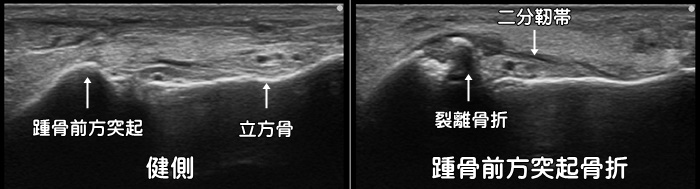

踵骨前方突起骨折・二分靭帯損傷

足首の捻挫では一般的には前距腓靭帯が損傷しますが、場合によっては二分靭帯と呼ばれる靭帯を損傷します。更に二分靭帯に引っ張られるように踵骨前方突起と呼ばれる骨の出っ張りが裂離骨折を起こす事もあります。レントゲンではなかなか見つけづらく、骨には異常なしと診断される事が多々あります。CTでは確実に診断できますが、足首の捻挫で初めからCTを撮影することは稀で、エコー検査であれば簡単に描出することが可能です。